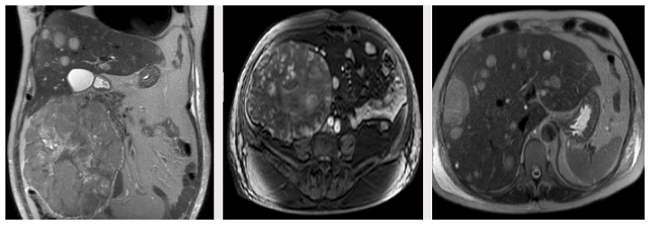

A magnetic resonance (MRI) of the abdomen showed a large retroperitoneal mass of 19x18x13cm, which displaced the ascending colon, the second duodenal portion, and the head of the pancreas. The lesion had a heterogeneous signal pattern in sequences with T1 and T2 information, predominantly hyperintense, with heterogeneous enhancement after administration of contrast medium. These findings suggested solid lesion with associated hemorrhagic residuals and multiple focal liver lesions that had a similar pattern (Figure 2).

The MRI showed heterogeneous signal on T1 and T2 secondary to the hemorrhage and necrosis areas in the tumor. 6 In the case presented here, the abdominal magnetic resonance showed a lesion of 19x18cm, which was highly suggestive of malignant neoplasm, as well as heterogeneous signal on T1 and T2, which together with the lesions observed in lung and liver, led to the diagnosis of tumor recurrence by ACC.